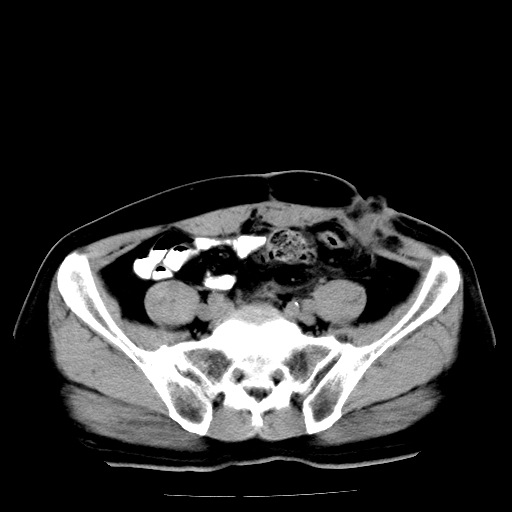

男,66岁,直肠癌术后一个月,化疗前ct检查。

前列腺大,直肠壁厚,造瘘术后

直肠癌造瘘术后改变,周围淋巴结转移

前列腺肥大

直肠癌造瘘术后改变,盆腔多发淋巴结转移

直肠癌造瘘术后改变,直肠周围软组织增厚,盆腔多发淋巴结转移。前列腺肥大。

盆腔内有很多点点,可能是淋巴结转移,建议增强。“直肠周围浸润”无法与术后斑痕鉴别,治疗后再说